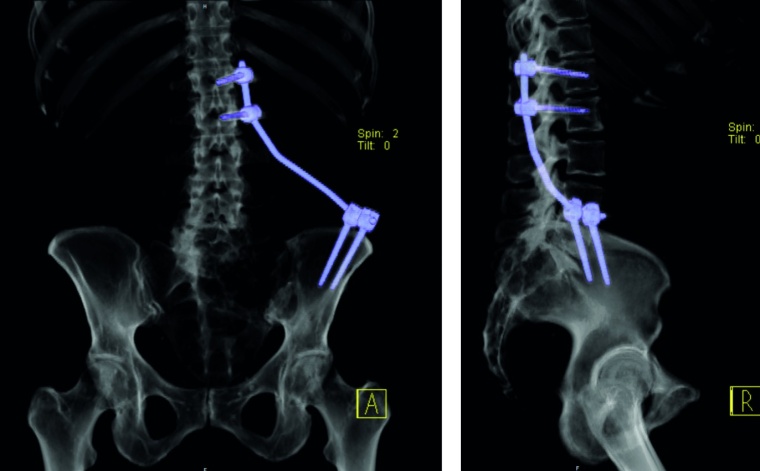

Fixateur interne: Haben die Osteolysen bereits Frakturen verursacht und weisen die betroffenen Wirbelkörper relevante Deformitäten auf, hat sich die perkutane überbrückende Stabilisierung mittels Fixateur interne bewährt (Abb. 2a und b). Der betroffene Wirbel kann ggf. additiv kyphoplastiert werden. Angesichts der sich zumeist anschließenden Radiatio verzichten wir jedoch zumeist darauf. Die Schrauben können je nach Knochenqualität zur Erhöhung der Stabilität wie üblich auch zementaugmentiert werden.

Sakrummetastasen: Stabilitätsgefährdende Metastasen am Sakrum (Abb. 3a) und am hinteren Beckenring werden zumeist mit einer mono- oder bilateralen vertebropelvinen Abstützung versorgt (Abb. 3b). Insbesondere das Os sacrum kann so aus der lasttragenden Kette herausgenommen werden. Vor allem bei Mammakarzinommetastasen kann mit der nachfolgenden Radiatio häufig eine so stabile Rekalzifikation erzielt werden (Abb. 3c), dass mitunter bei Beschwerden über dem Fixateur besonders bei schlanken Patienten eine Metallentfernung erwogen werden kann. Sollte das dorsale Os ileum mit betroffen sein (Abb. 4a) kann bei entsprechenden anatomischen Voraussetzung (Abb. 4b) auch weiter ventral auf den Beckenkamm abgestützt werden (Abb. 4c).